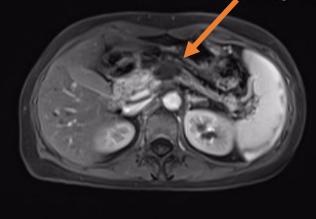

海扶刀在医学影像引导下,将体外低强度超声波聚焦于体内病灶,如同长了眼睛一般精准定位肿瘤。继而形成高能量的焦点,瞬态的高温(60℃—100℃)让肿瘤迅速凝固性坏死,而肿瘤以外组织却不受到明显损伤。通过控制焦点的三维组合运动,海扶刀以“点-束-片-块的”方式最终完成对整块靶组织的适形消融治疗。也就是说,海扶刀能“隔空打穴”,无需开刀,不会出血,通过超声波精准消灭肿瘤。

一位胰腺癌患者初诊时已是晚期,无根治性手术指征,来到青大附院就诊。传统治疗模式是以化疗为主,联合止痛、营养治疗。由于患者营养状态较差,治疗前评估其对化疗的耐受较差。在治疗肿瘤和担心副作用之间,患者和家属无数次徘徊和犹豫。海扶治疗为患者提供了一种新选择。肿瘤内科主任于壮组织会诊,制定详细方案,在麻醉科的配合下,于宁主任为患者完成全麻下胰腺病灶超声消融。手术后复查,该患者胰腺病灶“完美”消融,疼痛逐渐消失,恢复进食,体力状态较治疗前明显好转。接下来,患者在肿瘤内科接受了化疗,有足够的营养状态做支撑,没有出现严重的化疗相关副反应,肿瘤得到了长期的控制,生活质量也得到了极大改善。

胰腺癌被称为“癌中之王”,虽然发病率不高,但死亡率很高。患者初次诊断时大多已经发展为局部晚期或出现转移,失去手术机会。海扶刀治疗给胰腺癌患者带来多方面的改善。一是能快速缓解疼痛。九成伴有疼痛的患者通过一次治疗就能够有效缓解疼痛,明显改善生活质量。二是快速让肿瘤坏死,再联合化疗、放疗等其他治疗方式,大大延长患者生存时间和质量。近3年的研究结果显示,局部晚期(尚未转移)胰腺癌患者应用上述联合方式治疗后平均生存时间已超过2年。“癌中之王”尚且能被遏制,海扶刀对恶性肿瘤治疗效果可管窥一豹。